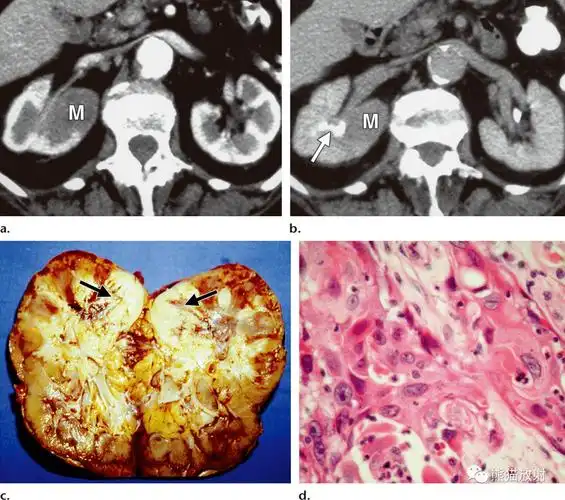

肾盂肾盏尿路上皮癌丨不常见影像表现